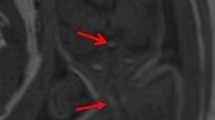

Because spatial resolution is increased on ultrasound, the morphology of the corpus callosum is better appreciated in good sonographic conditions than with MRI. The anterior part of the corpus callosum in particular is usually poorly visualized using MRI due to the thinness of the interhemispheric fissure and MRI is usually not helpful for diagnosing corpus callosum partial agenesis or for characterizing callosal dysgenesis [2]. Tubulonodular lipomas are easily depicted by ultrasound and do not require MRI [2]. On the contrary, curvilinear lipomas are much more challenging to diagnose because they may be very subtle on ultrasound, whereas fat T1 intensity is usually absent on fetal MRI. Therefore, particularly in a short corpus callosum, MRI is required to look for abnormal T2 intensity of the lipoma (Fig. 2) [10].

A fetus at 30 weeks of gestation with a curvilinear pericallosal lipoma revealed on ultrasound by a short corpus callosum. a A sagittal T2-weighted MRI slice shows marked hypointensity of the corpus callosum, which is too short with an absence of development of the rostrum and the splenium. Even though no abnormal signal intensity was observed on the T1-weighted sagittal slice (not shown), the marked T2-hypointensity suggested pericallosal lipoma. b A T1-weighted sagittal slice at 3 months of age shows linear hyperintensity lining the corpus callosum, in keeping with a curvilinear lipoma